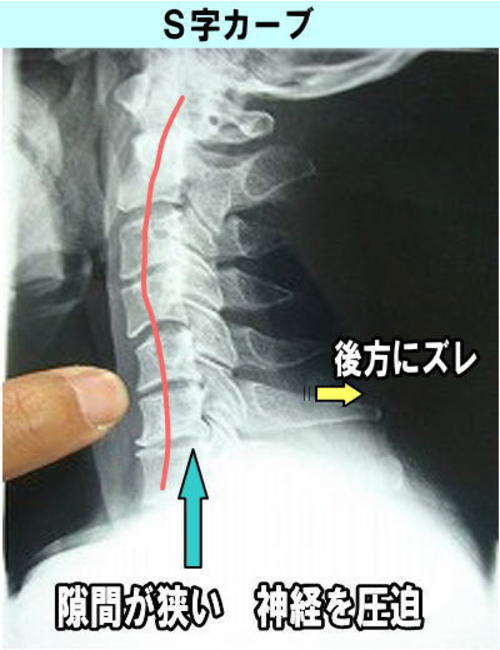

当オフィスの中心であるガンステッド・テクニックは、椎骨(関節)の後方変異を重視する施術方法です。

神経圧迫は、椎骨が後方にズレることで起こります

写真上のように、頸椎は理想であれば、前方にカーブしているのが正常です。

頸椎を過度に捻じるような矯正方法では、後方にズレている椎骨が前方に正しく戻ることは理屈に合いません。又、神経は捻じる力には弱いので逆に神経圧迫が強くなる可能性があります。当オフィスは、危険な身体を強く捻じる施術ではなく、圧迫している根本原因の後方にズレた椎骨を前方の正しい位置へ戻して、圧迫を取り除くことに全力を尽くすオフィスです。

長時間のパソコン作業や携帯電使用により、最近の多くの人は、うつむき加減での生活習慣が殆どで、写真下のように神経の通り道である頸椎()の前湾カーブが消失している人が多く、その為、圧迫が起こり様々な不快な症状が現れることが多いです